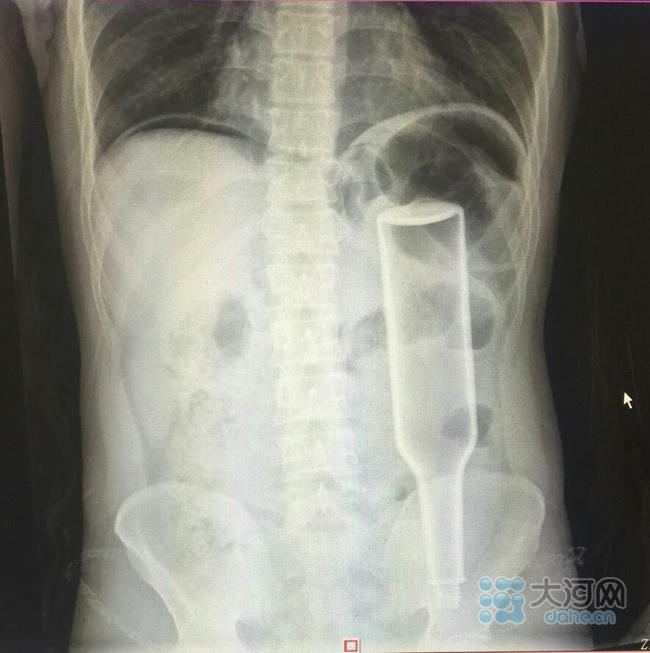

看这片子,花露水瓶子已经很“深入”了。

从检查片来看,瓶子已经塞到了他的直肠和乙状结肠的交界处,这是一个拐角处,瓶子死死地卡在这里,且显示右侧膈下有游离气体,提示消化道穿孔,张春礼大夫判断王某左侧大肠穿孔,于是当即联系手术室实施急诊手术。